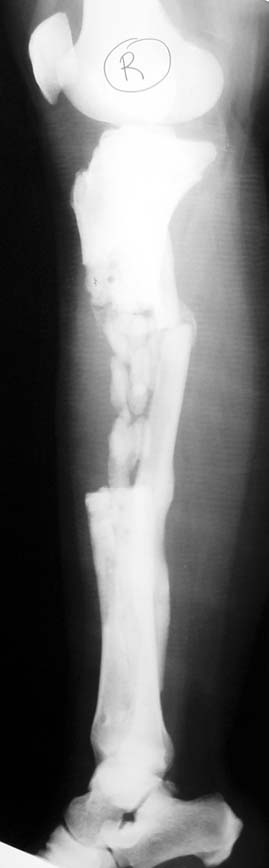

Chronic osteomyelitis leads to necrosis of bone and soft tissues. Dead bone is a nidus which hosts pathogenous microorganisms. Defence mechanisms of the host is usually not in optimum condition to deal with microorganisms. Antibiotics can’t reach the infection site because blood flow is disrupted. For these reasons, dead bone has to be completely removed by radical debridement.

Appropriate radical debridement necessitates excision of all necrotic bone and soft tissues, and frequently causes instability at the involved extremity. The remaining bone and soft tissue defect has to be fixed and reconstructed. The distraction osteogenesis method of Ilizarov is used successfully for achievement of union, correction of the deformity, elimination of limb length inequality and reconstruction of segmental bone defects.

Case 2